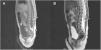

Se realizó una ecografía lumbar como parte de la valoración inicial de la niña, sin encontrarse ninguna anormalidad estructural. Pocos meses después, a pesar de que la lesión había disminuido de tamaño, se solicitó una resonancia magnética (RM), observándose un lipoma de 4mm asociado al cono medular y una médula espinal anclada (fig. 2). Por otro lado, con esta prueba se descartó la presencia de alguna anormalidad urológica. La médula espinal anclada fue tratada por el servicio de neurocirugía pediátrica (fig. 3), con una respuesta clínica posterior adecuada y un desarrollo psicomotriz normal.

Se solicitó una ecografía de la región afectada, con lo que se constató la presencia de un sinus dérmico persistente. La RM mostró además un lipoma a nivel de filum terminale (fig. 5). Con estos hallazgos se derivó al paciente para valoración por urología descartándose alguna anomalía a este nivel. Dada la ausencia de clínica neurológica, en la unidad de neurocirugía pediátrica se decidió realizar únicamente seguimiento.